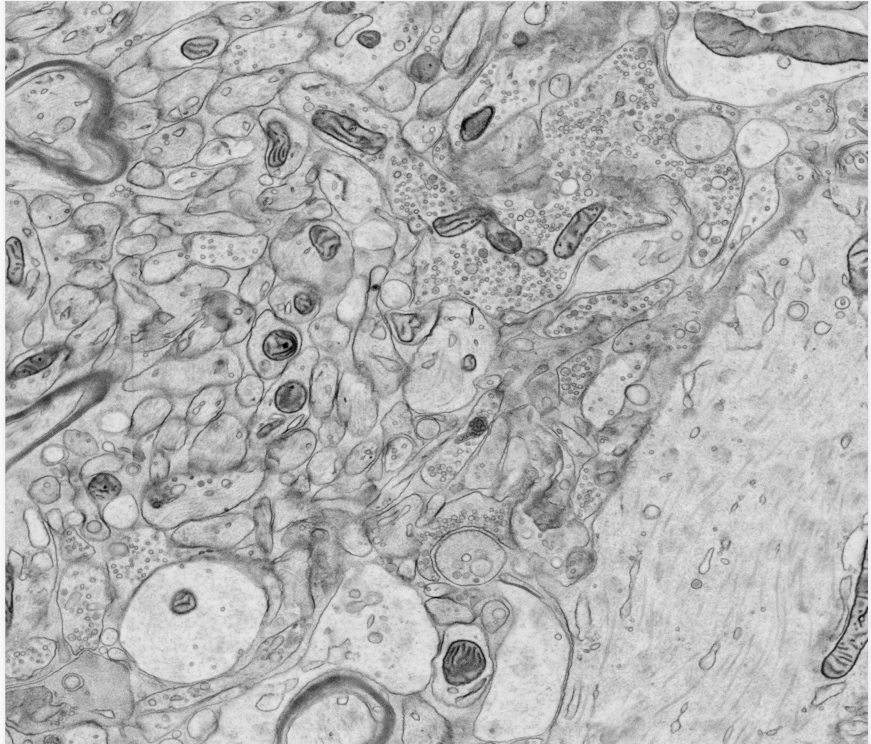

北京大学医学部黄新瑞鼠脑组织

发布时间:2022-01-06